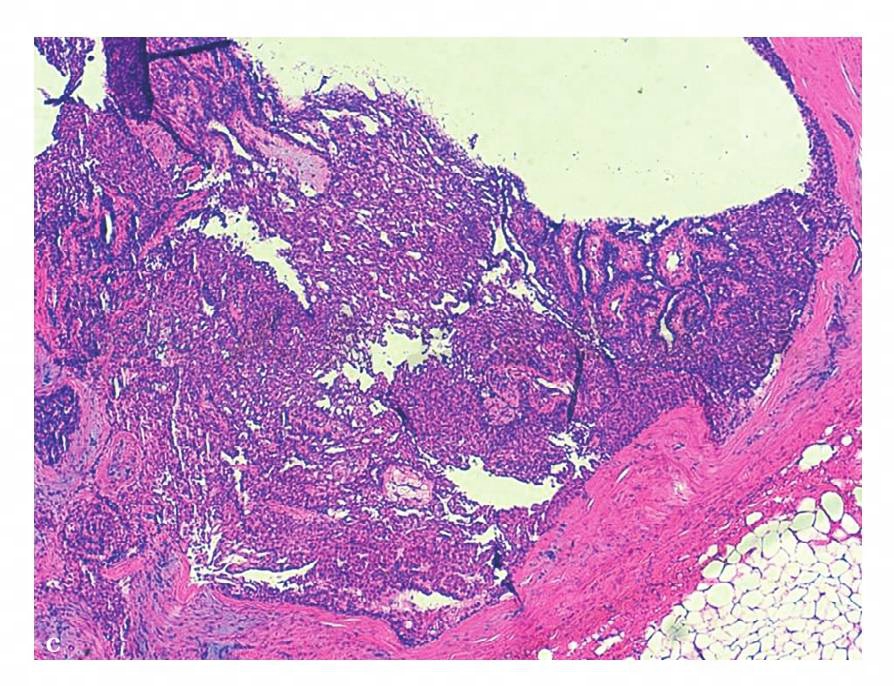

图18 c,病理示镜下所见腺体扩张拉长呈裂隙状